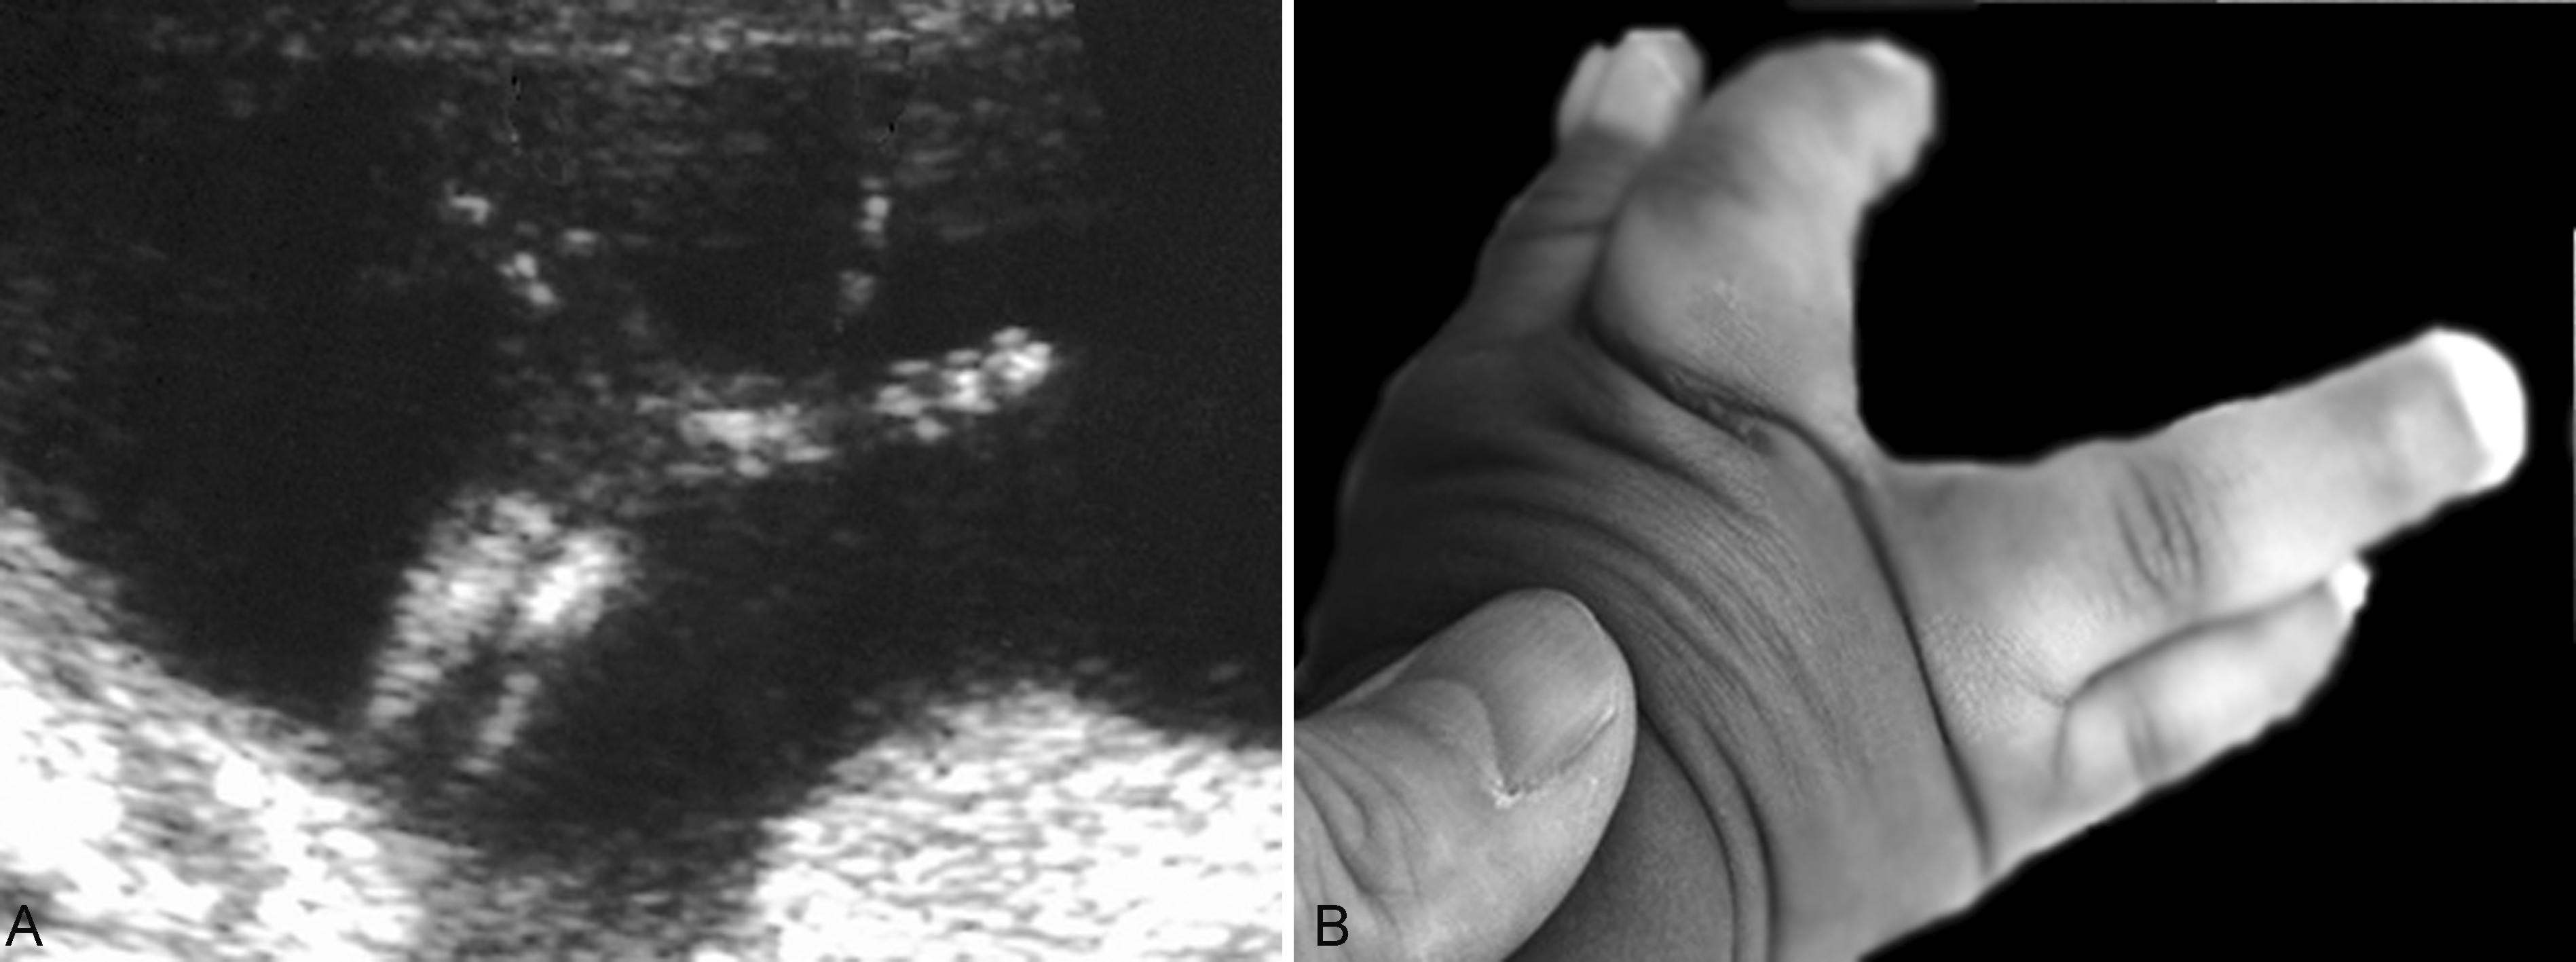

3.手和足的评估 手(足)的评估包括手(足)的大小、形态异常和多指(趾)、短指(趾)畸形等,如剪刀手(图5)、凉鞋足、多指(趾)、并指(趾)等,但已经公布的国内外超声检查规范中都没有把肢端掌(跖)骨和指(趾)骨的超声检查作为产前超声检查必须的内容。

图5胎儿剪刀手畸形:A:剪刀手声像图;B:出生后手部照片